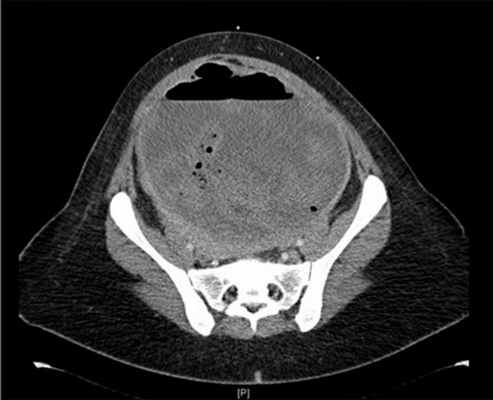

Рис. 7. КТ брюшной полости и таза, демонстрирующая пиомому

Рис. 8. Аксиальное сечение КТ: миома с газом и уровнем жидкости